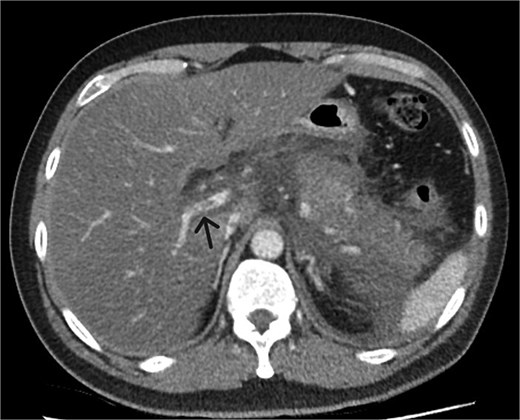

A 39-year-old male presented with one week of worsening epigastric pain radiating to the back, with vomiting, jaundice, and dark urine. His past medical history included depression and alcohol-related liver disease without cirrhosis. On admission he was afebrile, had a soft abdomen with epigastric tenderness worse on palpation, tachycardic, and normotensive. Initial investigations showed a lipase of 2600 U/L, C-reactive protein 238 mg/L, lactate 3.4 mmol/L, and bilirubin 100 μmol/L (Table 1). Abdomen and pelvic computer tomography (CT) demonstrated body and tail pancreatitis, fat stranding, portal vein thrombus, and early necrosis signs, with no choledocholithiasis (Figs 1–3).

Axial CT image demonstrating non-occlusive portal vein thrombus (depicted by arrow).